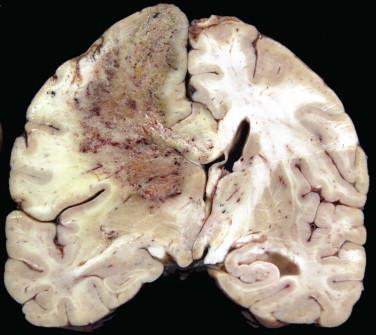

What caused this vasogenic edema?

Cerebral abscess